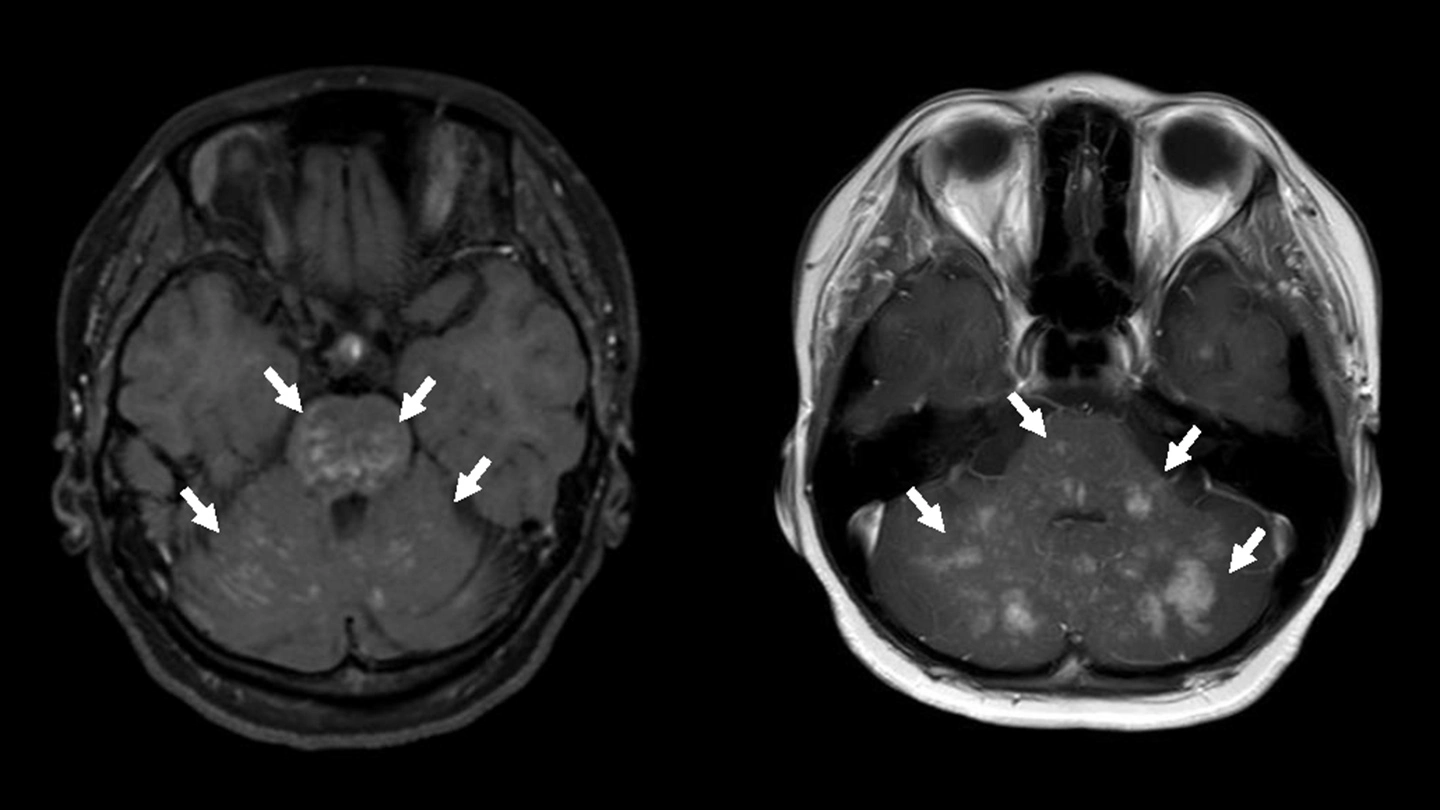

本研究で報告した2症例の頭部MRI(造影T1強調)画像:小脳と脳幹に、白く造影される点状・結節状の病変を多数認め(矢印)、CLIPPERSに類似する所見を示した。

CLIPPERSは、脳幹や小脳を中心に、脳や脊髄といった中枢神経に炎症が生じる疾患です。MRI検査で小さな病変が多数認められ、ステロイド治療が有効であることが特徴とされています。一方で、炎症が起こる原因は十分に解明されておらず、診断や治療方針の判断が難しい場合もあります。

CLIPPERS:Chronic lymphocytic inflammation with pontine perivascular enhancement responsive to steroidsの略。脳幹(特に橋)や小脳を中心に脳や脊髄に炎症が起き、造影MRIで小さな点状の造影所見が多数みられることが特徴。多くの例でステロイド治療に反応するが、なぜ炎症が起きるのかは十分に分かっていない。